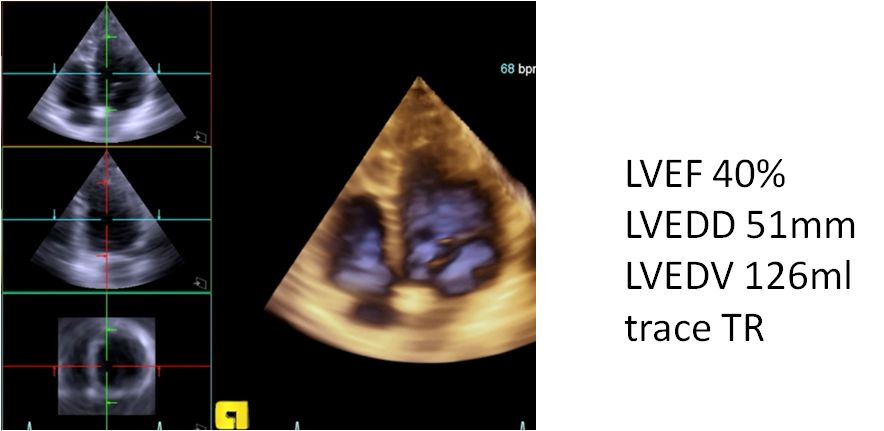

▶▷ 2018年10月29日-31岁男性,心力衰竭入院